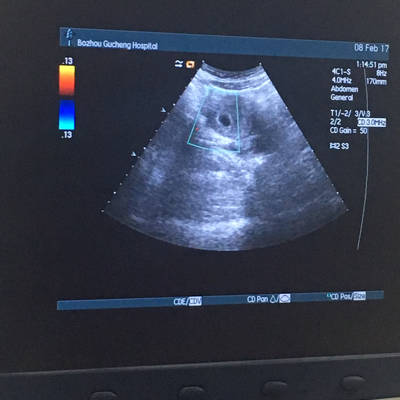

怀孕40天有很小的红色血块流出,查b超显示有孕囊,是先兆流产吗?

诊断 处理发病以来,未用药,二便正常,无腹痛随访 讨论停经43天,阴道不